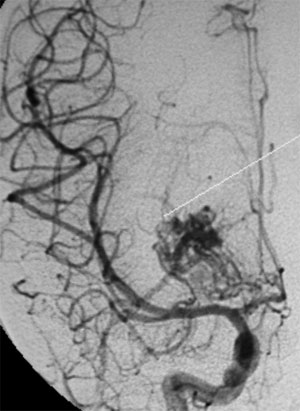

CASO 1 : Embolización de MAV frontal izquierda que presentó hemorragia cerebral resultando en hemiparesia derecha y trastorno del lenguaje

Angiografía antes del tratamiento por embolización. Se muestran por lo menos dos aneurismas en el interior del ovillo malformativo